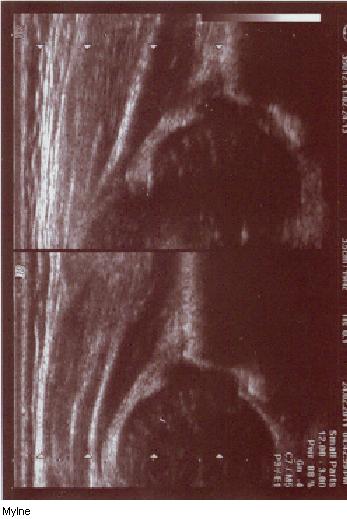

powyżej staw prawidłowy Typ I dach kostny dobry;brzeg kostny tępy ;dach chrzestny pokrywa

dolne zdjęcia

strzałki pokazują obrabek(czerwona):brzeg kostny (żółta);gałąż dolna(niebieska) ,

prawidłowy przebieg linii dachu kostnego(niebieska) stycznie do echa gałęzie dolnej i echa brzegu kostnego ;

linii dachu chrzęstnego (czerwona) stycznie do brzegu kostnego i przez środek geometryczny obrąbka i

linii podstawnej ( żółta